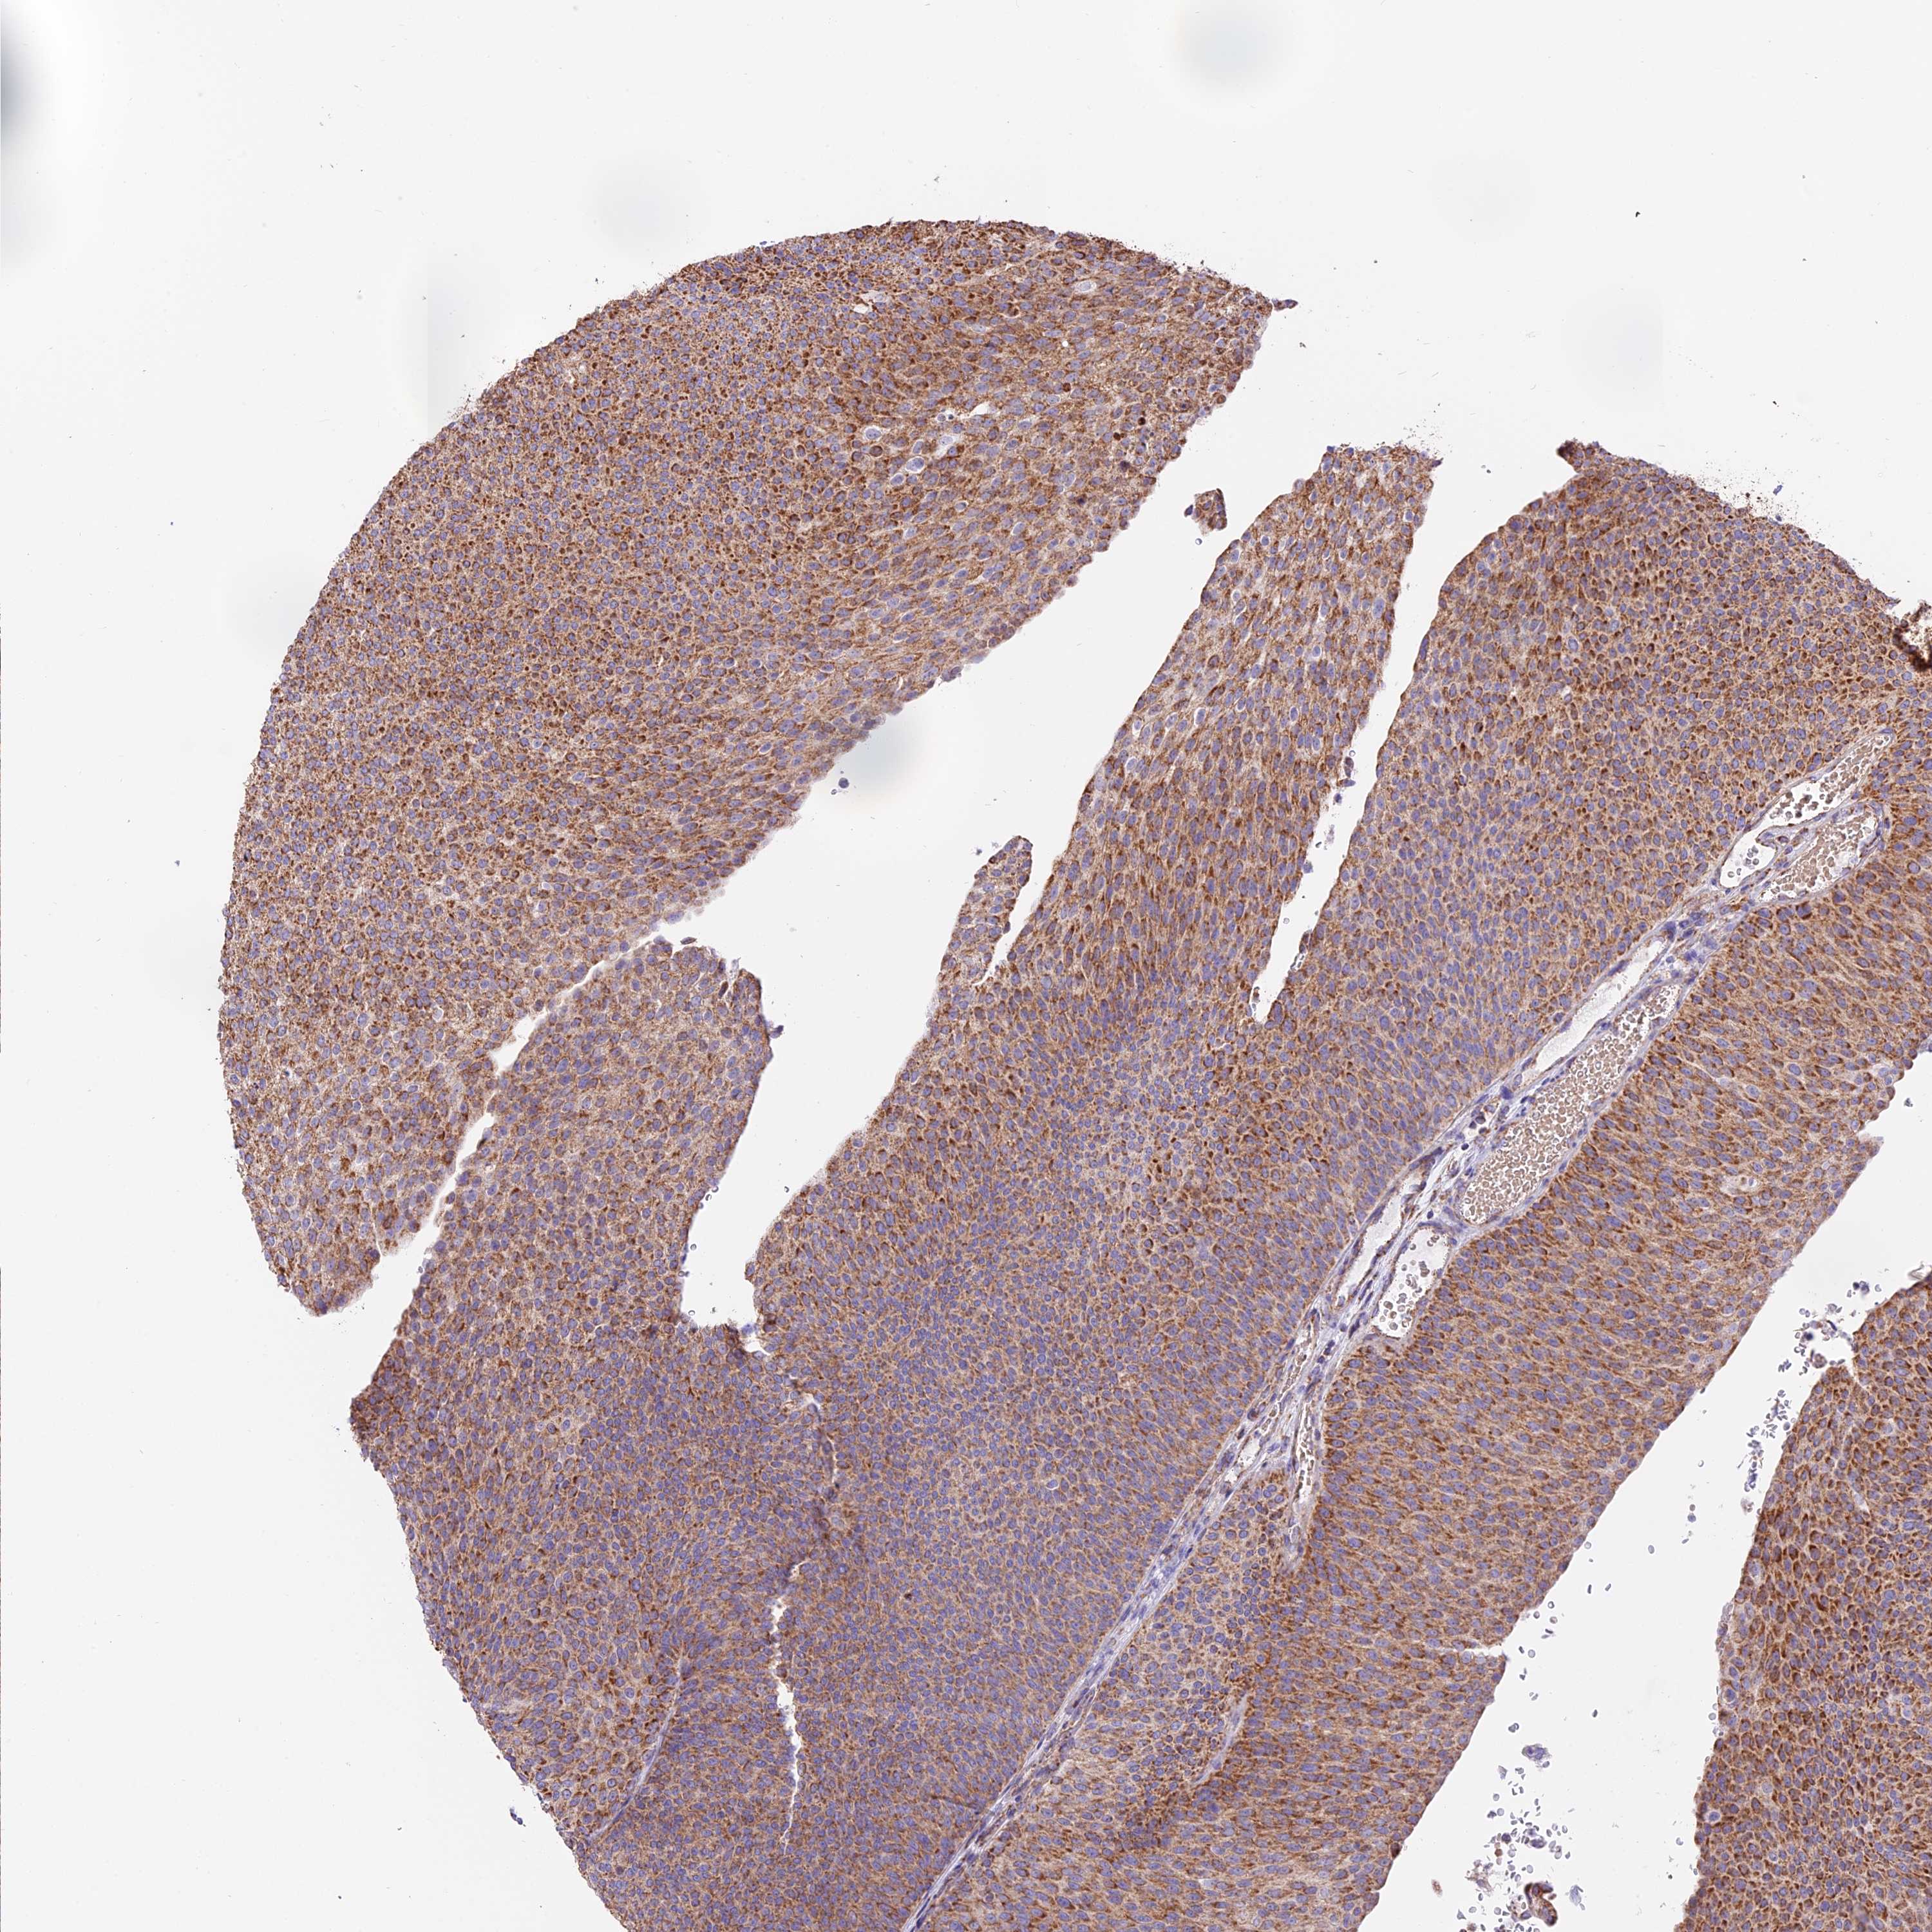

UROTHELIAL CANCER - Protein expressioni

A mouse-over function shows sample information and annotation data. Click on an image to view it in a full screen mode. Samples can be filtered based on level of antibody staining by selecting one or several of the following categories: high, medium, low and not detected. The assay and annotation is described here.

Note that samples used for immunohistochemistry by the Human Protein Atlas do not correspond to samples in the TCGA dataset.

Antibody stainingi

Antibody staining in the annotated cell types in the current human tissue is reported as not detected, low, medium, or high, based on conventional immunohistochemistry profiling in selected tissues. This score is based on the combination of the staining intensity and fraction of stained cells.

Each image is clickable and will lead to virtual microscopy that enables deeper exploration of all samples and also displays staining intensity scores, fraction scores and subcellular localization as well as patient and tissue information for each sample.

Antibody HPA041600

Urothelial carcinoma, Low grade